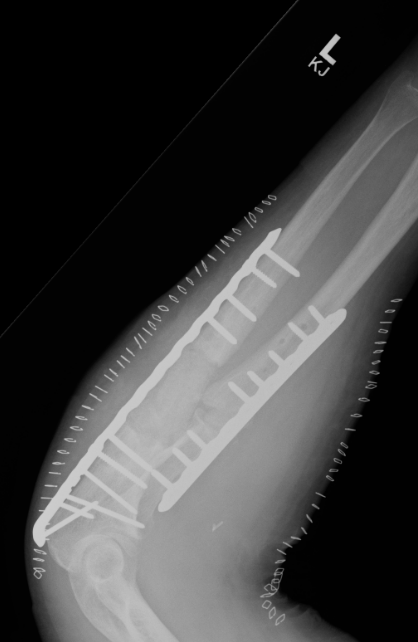

ORIF with plates

Intramedullary fixation

ORIF with DCP plates

Fixation with DCP plates

Revision compression plating + drill intra-medullary canals + autograft

- 35 forearm nonunions treated with revision compression plating and bone grafting

- average defect 2 cm

- 100% union